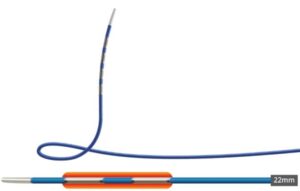

Een 68-jarige vrouw werd verwezen in verband met verdenking op een perihilair cholangiocarcinoom, Bismuth type IIIb (figuur 1). In verband met icterus en mogelijke hemihepatectomie links werd er een plastic endoprothese in de rechter ductus hepaticus geplaatst. De galwegen links werden bewust niet gecontrasteerd. Tevens werd een brush afgenomen die de diagnose adenocarcinoom bevestigde. Vanwege snel toegenomen vaatbetrokkenheid kwam patiënte niet meer in aanmerking voor resectie of levertransplantatie. Derhalve werd gestart met palliatieve systeemtherapie en werd de plastic stent electief gewisseld voor een ‘uncovered’ metalen stent (uSEMS). Aangezien er, op basis van het lage bilirubinegehalte (11 μmol/L), reeds voldoende drainage met een unilaterale stent was bereikt, werd er niet aanvullend bilateraal gedraineerd. In studieverband (RACCOON-pilot [NL9144]) werd de stenose geableerd met endobiliaire radiofrequente ablatie (eRFA), met het doel om de duur van de stentdoorgankelijkheid te verlengen. Met een 22 mm ELRA-electrode (Taewoong Medical) werd de stenose 90 seconde geableerd met 7 watt en target temperatuur van 75 graden (figuur 2). De ductus cysticus werd niet in het traject betrokken om een post-procedurele cholecystitis te voorkomen. Na verwijderen van necrotisch materiaal met een extractieballon werd een 80 x 8 mm uSEMS geplaatst (figuur 3). 5 maanden later ontwikkelde patiënte klachten passend bij stentobstructie. Er werd opnieuw eRFA verricht van de stenose in de stent en een tweede 60 x 8 mm uSEMS in de reeds aanwezige stent geplaatst (figuur 4). Weer 5 maanden later ontwikkelde patiënte recidiverende klachten. Er werd opnieuw eRFA verricht, maar ditmaal werd geen aanvullende stent geplaatst (figuur 5). Patiënte overleed 5 maanden later zonder terugkerende obstructie, 2 jaar na de diagnose.